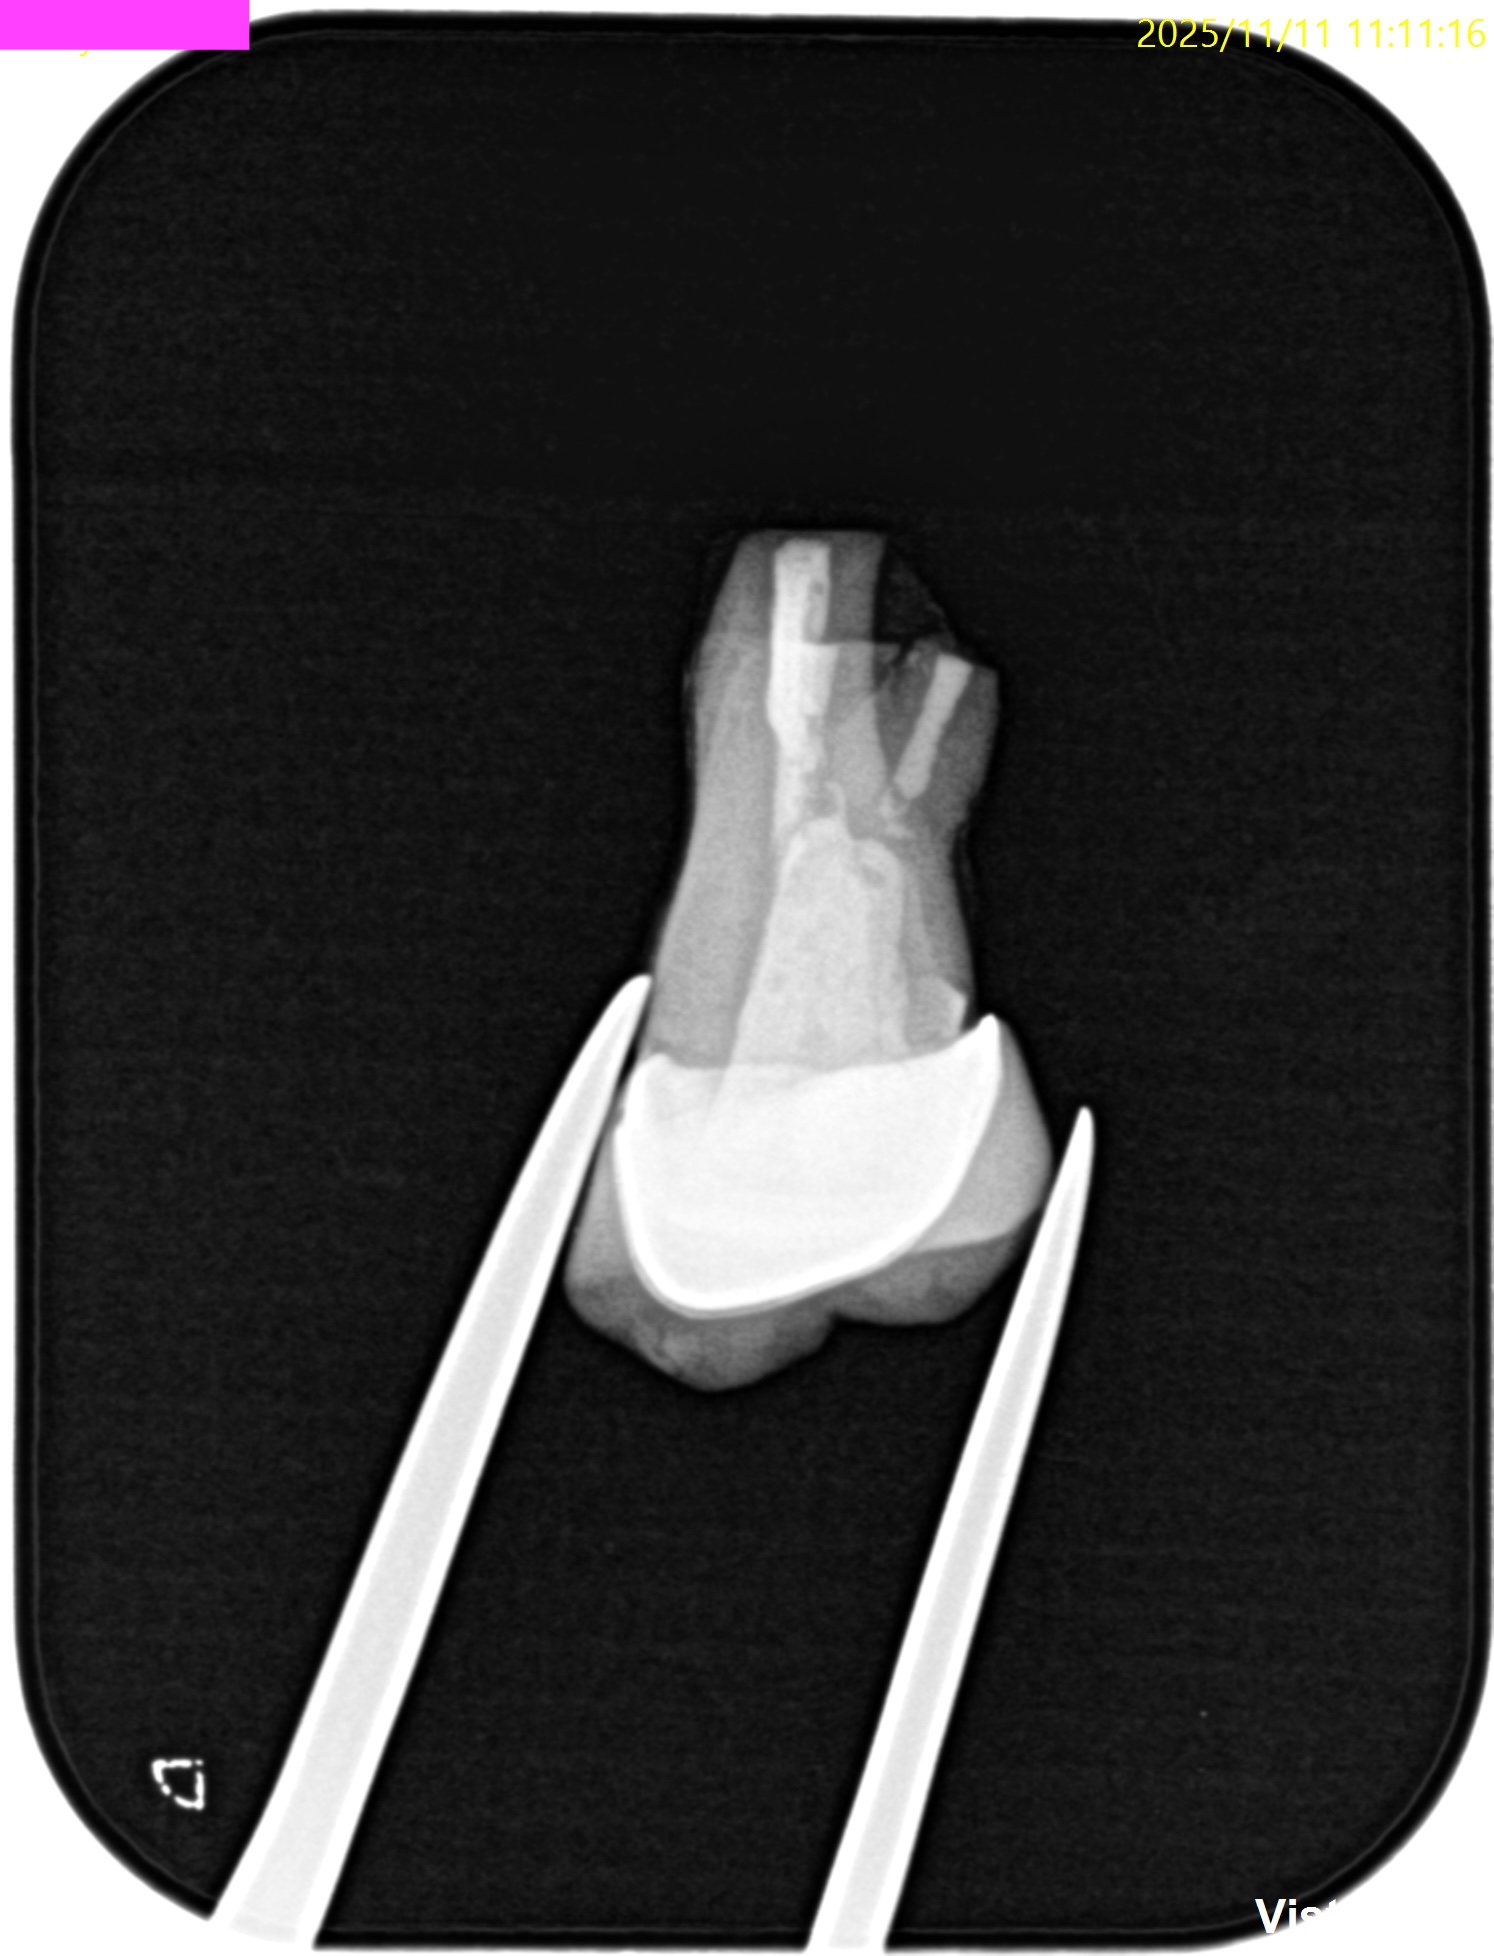

PA(2025.11.11)

MB

DB

P